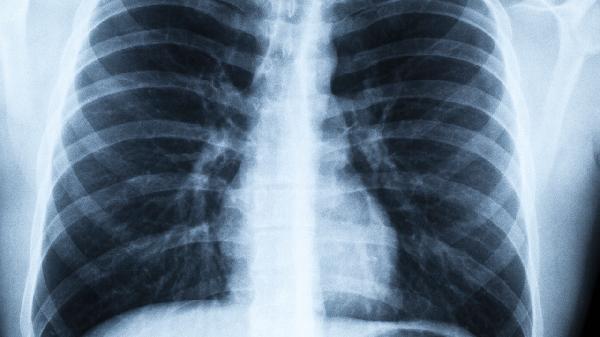

肺栓塞这个“隐形杀手”来得总是猝不及防,前一秒还在谈笑风生,下一秒可能就呼吸困难。别以为它只会找上长期卧床的病人,那些经常久坐办公的年轻人同样在危险名单上!今天就教你识别那些容易被忽视的危险信号,关键时刻能救.命。

一、这些症状可能是肺栓塞在敲门

1、不明原因的呼吸困难

突然感觉像被人捂住口鼻,即使安静坐着也喘不上气。这种窒息感会随着体位变化加重,平躺时尤其明显。

2、胸痛像被刀刺

疼痛集中在胸骨后方,深呼吸或咳嗽时加剧。很多人误以为是心脏病发作,其实疼痛性质完全不同。

3、咳血不容忽视

痰中带血丝或粉红色泡沫痰,这是肺动脉高压导致肺泡出血的典型表现。